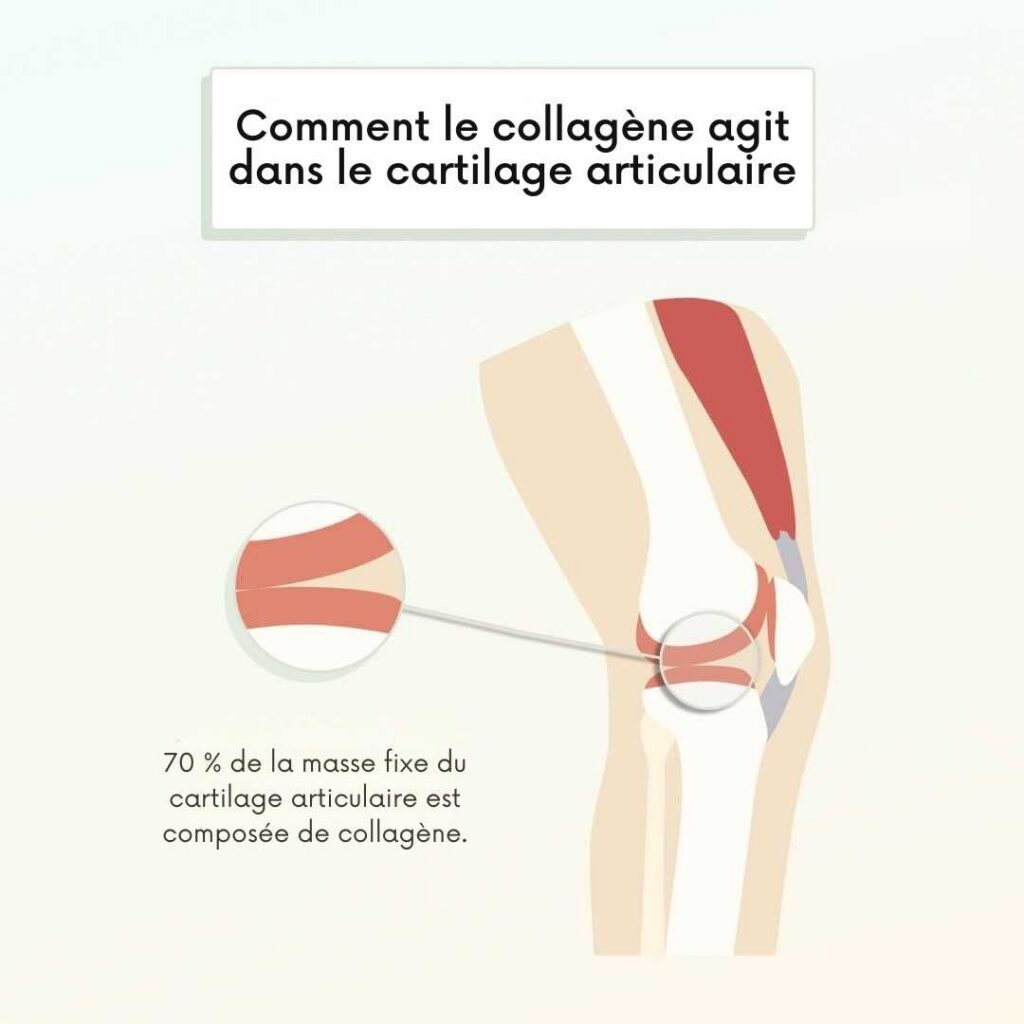

Le collagène représente 70% du cartilage de vos articulations. C’est lui qui assure le coussin protecteur entre vos os. C’est lui qui permet à vos genoux, hanches, épaules et doigts de bouger sans friction, sans douleur.

Et à partir de 25 ans, vous en perdez 1 à 1,5% chaque année.

Le calcul est simple :

- À 50 ans : vous avez perdu 35 à 40% de votre collagène

- À 60 ans : il ne vous reste que la moitié

- À 70 ans : votre cartilage fonctionne avec un tiers de ses capacités

C’est pour ça que les douleurs s’installent progressivement. Ce n’est pas « l’âge ». C’est un déficit que personne ne vous a appris à combler.